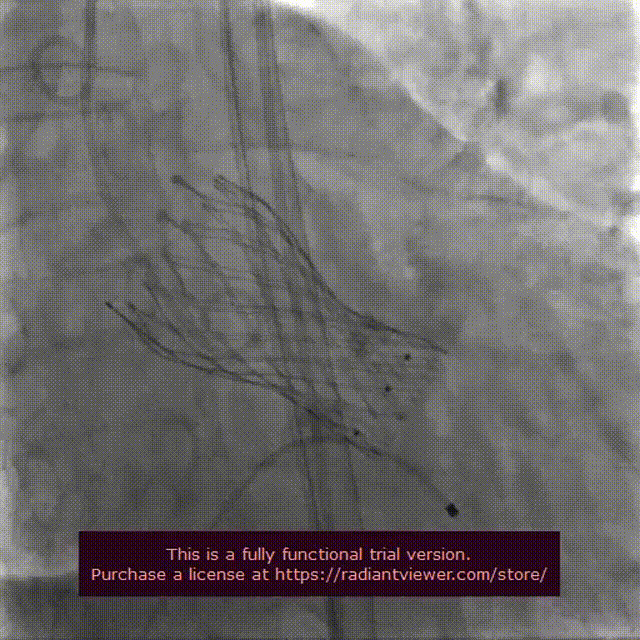

VenusA-Plus®释放过程

瓣膜完整形态